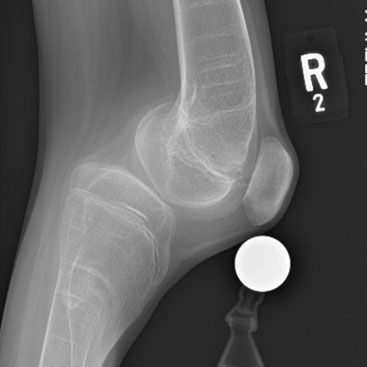

Pediatric Patellofemoral Instability: Beyond the MPFL

Current Concept Review

Kenneth M. Lin, Alexandra T. Mackie, Alexandra H. Aitchison, Aristides I. Cruz Jr., Corinna C. Franklin, Joseph T. Molony Jr., Kevin G. Shea, MD, Daniel W. Green, Peter D. Fabricant